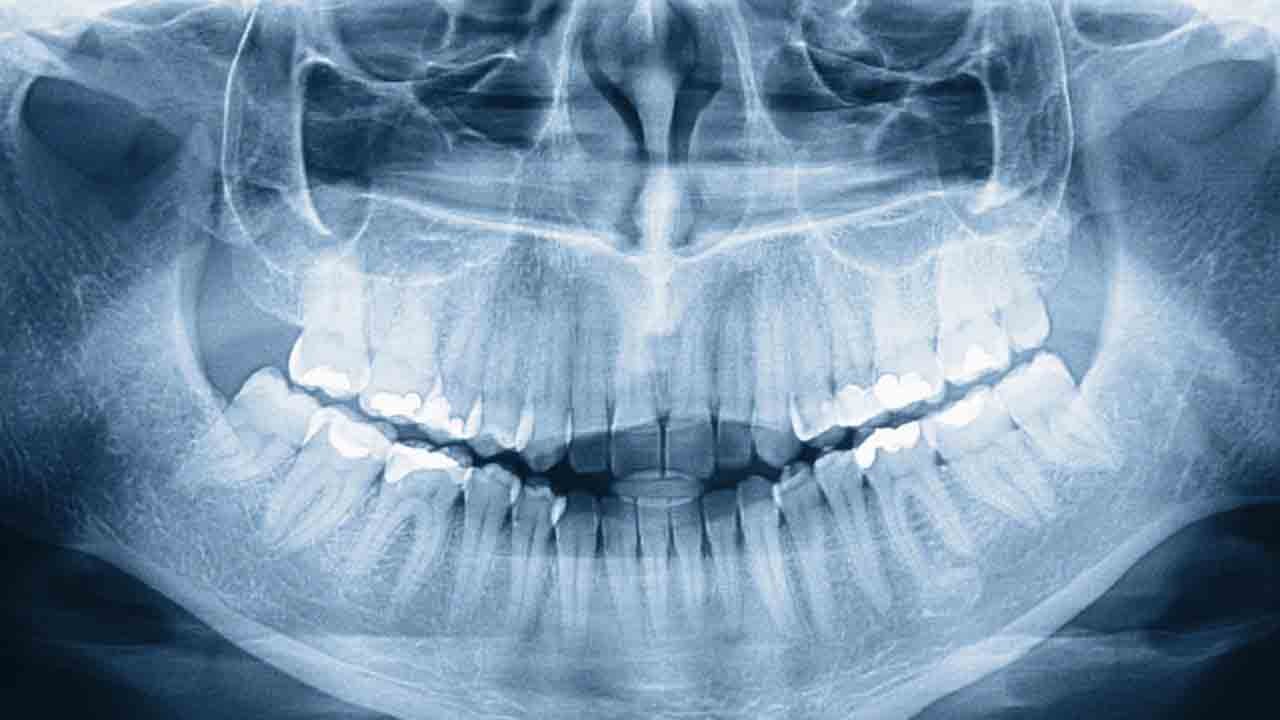

32 değil 42 diş: Fark etmeden dünya rekoru

Standartta 32 diş bulunan insan ağzı, nadir görülen “hiperdonti” nedeniyle bazen bu sınırı aşabiliyor; Malezyalı Prathab Muniandy’nin ağzında tam 42 diş bulunması ise ona dünyanın en çok dişe sahip erkeği unvanını kazandırdı.